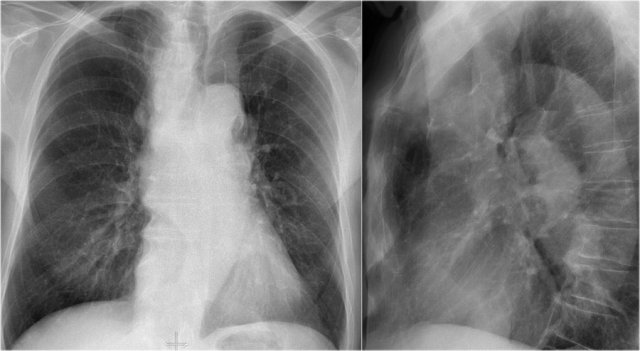

Old films

It is extremely important to always compare with old films, as we will demonstrate in this case.

Actually someone said that the most important radiograph is the old film, since it gives you so much information.

For instance a lung mass, which hasn't changed in many years is not a lung cancer.

First study the chest films.

Based on these films, you could make the diagnosis of congestive heart failure, but the findings are subtle.

Continue with the old film...

Scroll back and forth to the old film.

Once you compare the chest film to the old one, things become more obvious and you will be much more confident in your diagnosis of congestive heart failure:

- The size of the heart is slightly increased compared to the old film, but was already large on the old film.

- The pulmonary vessels are slightly increased in diameter indicating increased pulmonary pressure.

- There are maybe some subtle interstitial markings as a result of interstitial edema.

- There is pleural fluid bilaterally. Notice that the infero-posterior border of the lower lobes has changed in position.